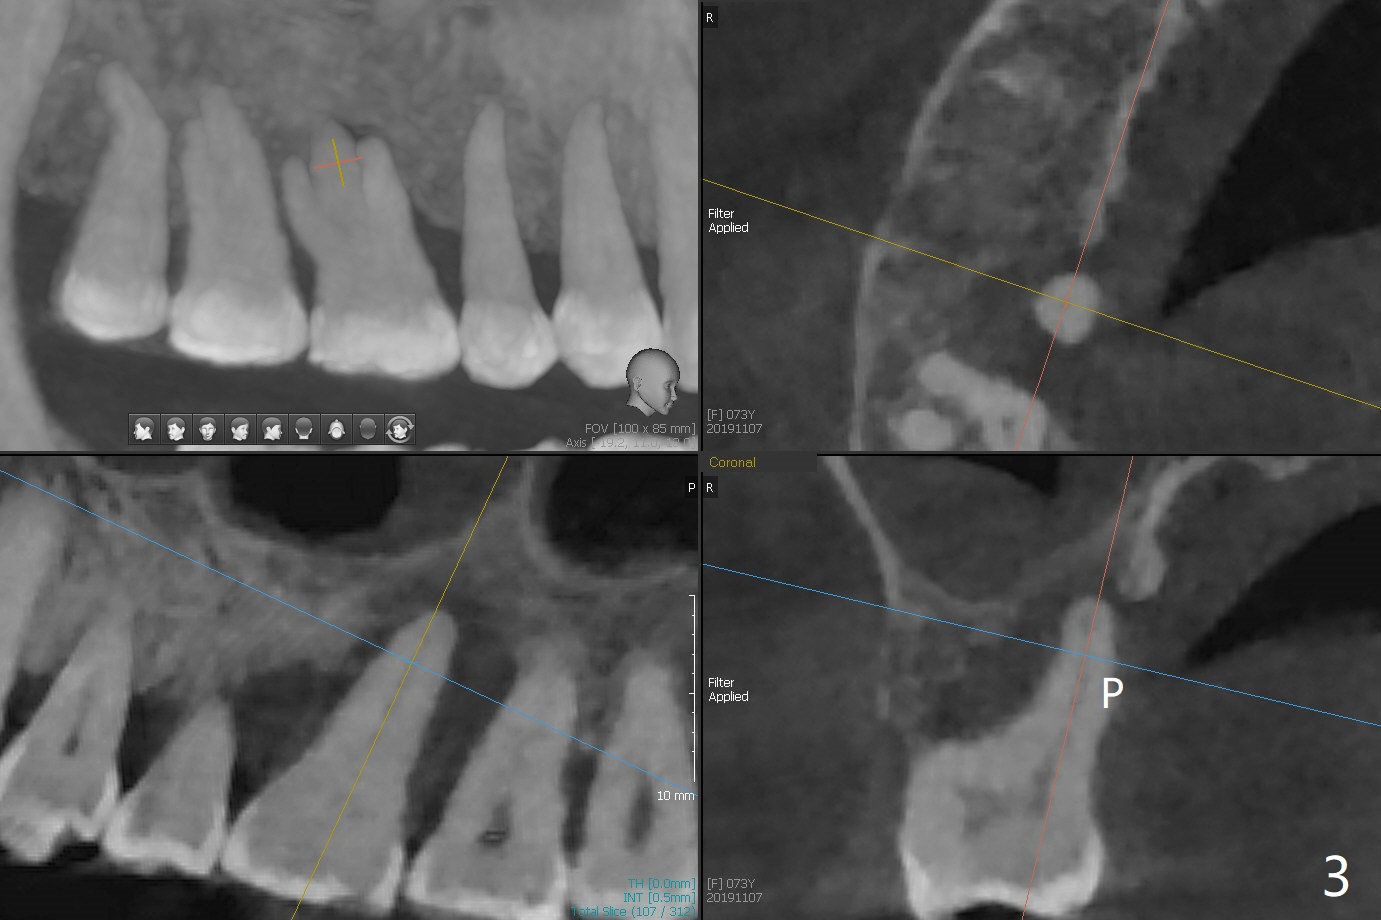

A 73-year-old woman with controlled diabetes has cold and hot sensitivity of the tooth #3. Although the bone loss is striking (Fig.1), mobility is I with the deepest pocket DL ~6 mm. Endo ice induces pain. Extraction and guided immediate implant appears to be the best option (Fig.2 (5x7mm FC)). Note the bone height (2.9 mm) and the thick sinus membrane (M, Fig.2') . B: buccal. Bony defect will be filled with sticky bone and held in place with Cytoplast, while PRF for sinus lift. Because she is afraid of implant, RCT, followed by SRP and possibly periodontal surgery, seems to be viable because of the straight, not-so-narrow canals (Fig.3-5). Due to time constraint, immediate implant will be done free hand. Use IS cassette, since there are 3 and 4 mm stoppers. Prepare FC dummy and water lifter for sinus lift.